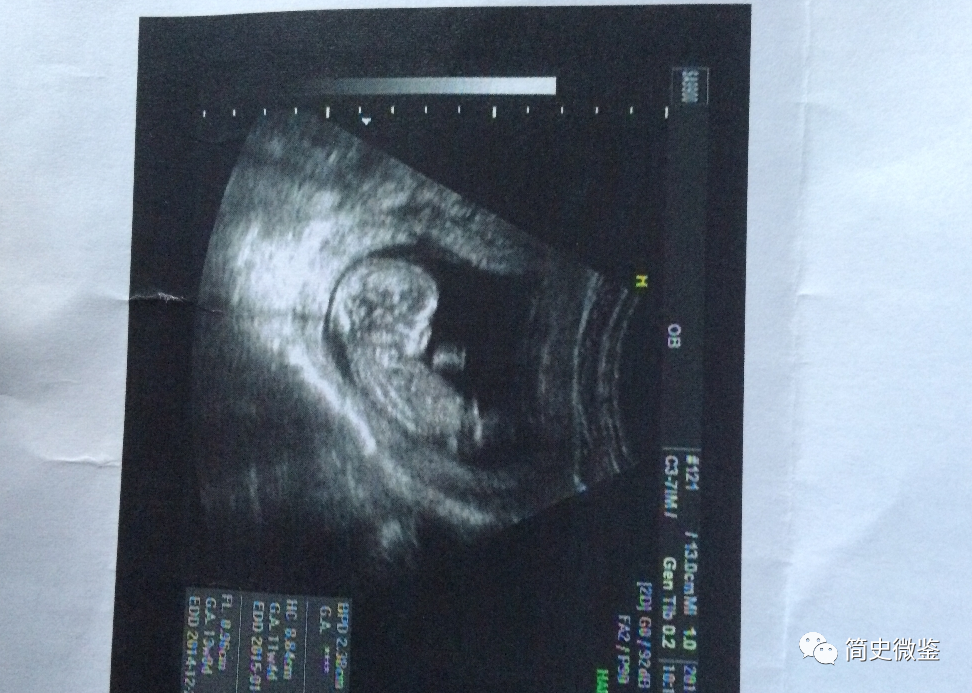

“倩倩已经怀有三个月的身孕!”

也就是说,倩倩的男友另有其人,或者说倩倩遇害的关键原因有可能是肚子里的那个孩子。

于是倩倩产生了与廖运端分手的想法,但这时,她却发现自己怀孕了。

由于这个孩子算是廖家的独苗,廖家人对倩倩也更加上心,还买了婚房,夹在中间的她左右为难,就返回了上海。